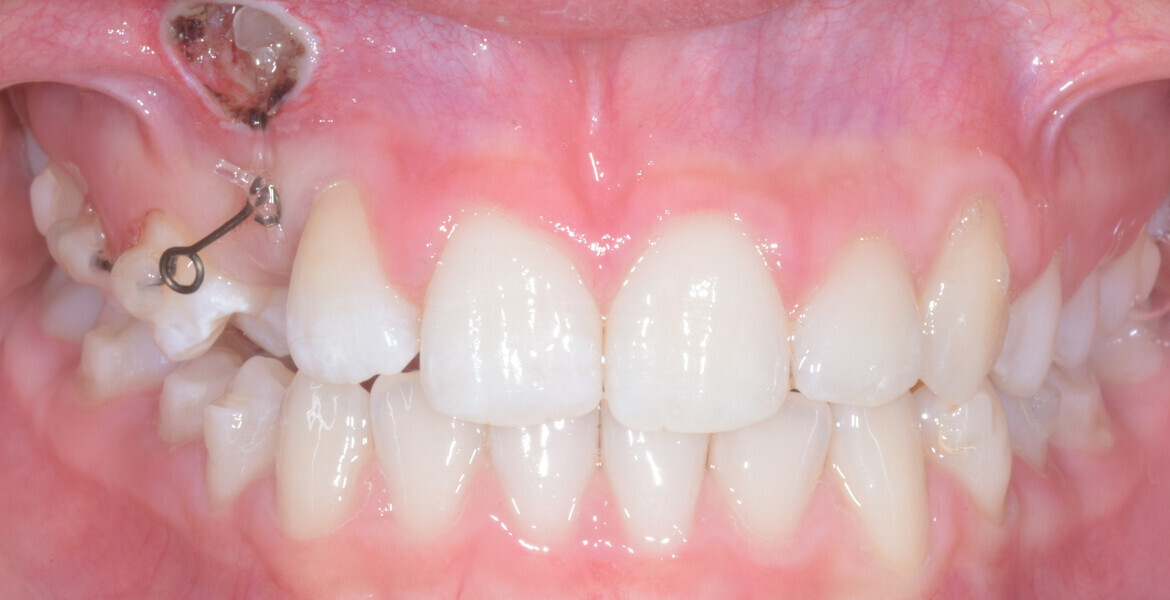

A 14-year-old female patient presented with the chief complaint of midline deviation and dental crowding in both arches. Facial analysis showed a hypodivergent growth pattern, a normal nasolabial angle, a harmonious profile and proper chin projection. Clinical examination revealed a Class III skeletal relationship (ANB = 0°) and Class I molar relationship. The maxillary right canine was absent, and this had led to space loss and mesial drift of posterior teeth on the right side, resulting in a slight Class II molar relationship. The maxillary left canine had erupted in a high position. The mandibular arch displayed crowding despite the agenesis of the right second premolar and the persistence of the primary molar (Figs. 3–11). The radiograph showed the probably premature loss of the maxillary right primary canine and consequently impacted maxillary right permanent canine, and the agenesis of the mandibular right second premolar and the mandibular right third molar (Fig. 12).

Fig. 3

Fig. 4

Fig. 5

Fig. 6